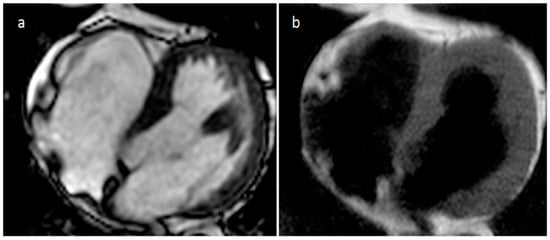

3.11. Echinococcus Cyst

| Echinococcus cyst | Adulthood | Myocardium, pericardium | Usually, asymptomatic | Typical hydatic cyst imaging characteristics | Well defined cystic mass with or without septations | Hypodense lesion with a wall, daughter cysts, peripheral calcifications | Hypo T1w, hyper T2w |